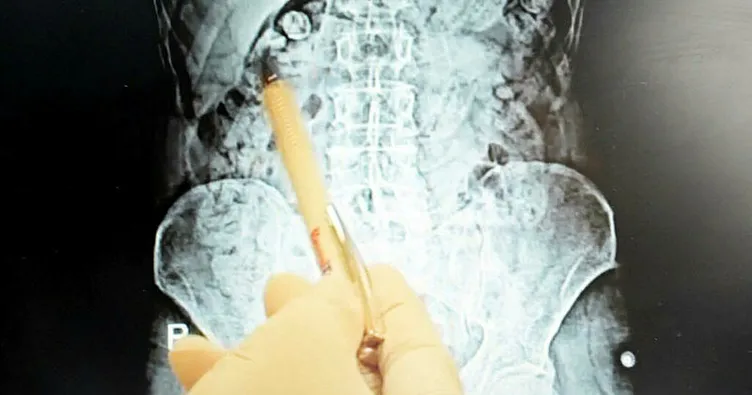

İl Emniyeti Narkotik Suçlarla Mücadele Şube Müdürlüğü ekipleri, Torbalı'da uyuşturucu satıcılarına yönelik çalışma kapsamında İran uyruklu E.M. ve P.S.'ye kimlik kontrolü yapmak istedi. Kontrolde herhangi bir suç unsuruna rastlanmazken, E.M. ve P.S.'nin davranışlarından şüphelenen polis, zanlıları gözaltına aldı. Uyuşturucu maddeyi kapsül halinde yutarak saklayabilecekleri ihtimali üzerine şüpheliler, hastaneye götürüldü. Hastanede çekilen röntgen filminde iki şüphelinin de mide ve bağırsaklarında 116 kapsül halinde toplam 810 gram metamfetamin bulundu. Yapılan cerrahi operasyonla uyuşturucu maddeler şüphelilerin vücutlarından çıkarıldı.